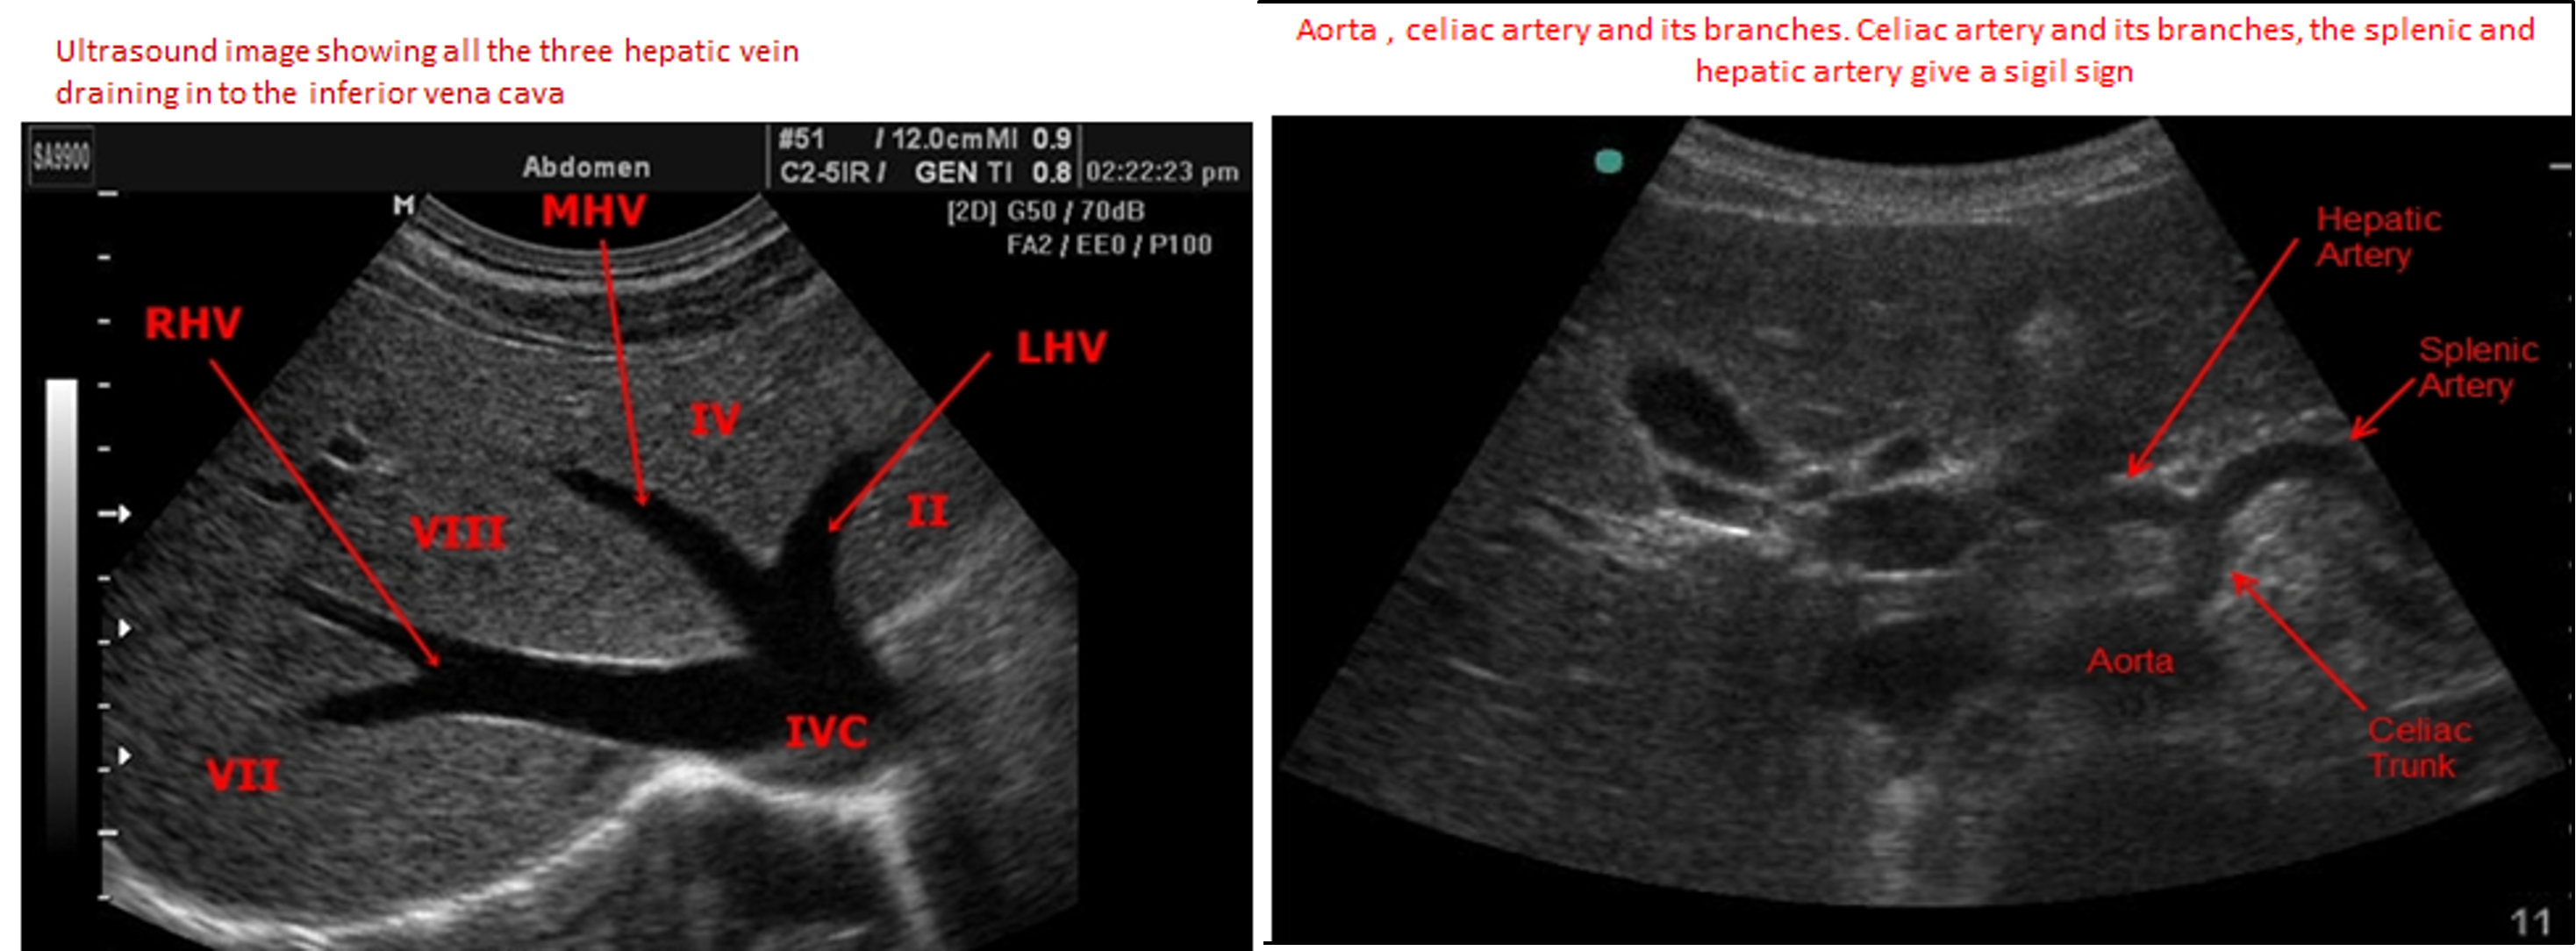

2nd Ultrasound of normal liver. showing the right , middle and left hepatic veins draining into the inferior vena cava as it penetrates the diaphragm.

Transverse image at the dome of the liver shows left and middle hepatic vein draining into the inferior vena cava. The homogeneous liver texture is well seen

- Sigil/// = Seagull sign